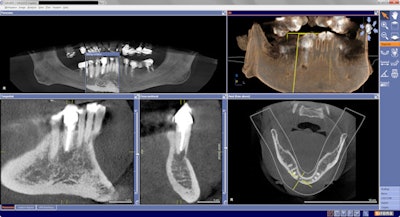

A previously treated endodontic tooth was failing. On initial review, I considered dismantling and retreating. The fill appeared to be short of the apex, but because of the extent of the swelling and level of pain, I wanted to evaluate in an enhanced 3D scan. The imaging led to my referral of this patient to an oral surgeon for an apicoectomy in an effort to retain this tooth.

Interestingly, the tangential view was similar to the periapical view, but the cross-sectional view influenced my decision.

Looking carefully, one can see that the fill was well-done, and the buccal lingual tooth length was not the same in the horizontal plane. I did not feel that retreatment could improve this situation. An extraction and bone graft would not be the first choice, as his dentition was extremely crowded in this area. Crown and bridge also would be challenging to say the least.

The tooth was treated with an apicoectomy and retrograde filling, which resolved his symptoms within a few days. He thanked me on a follow-up appointment for not performing any unnecessary treatment that would not have solved his problem.